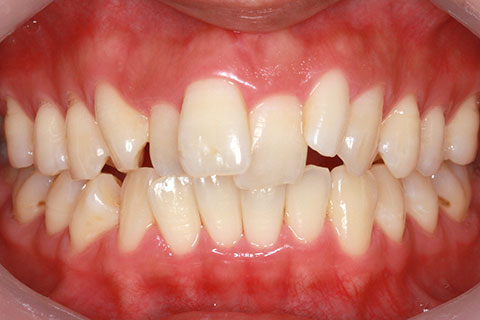

矯正期間18ヶ月

ハーフリンガル矯正2(上の歯のみ舌側矯正で治療)

治療前

治療中

治療後

- 年齢・性別

- 23歳女性

- 治療期間

- 1年6ヶ月

- 抜歯

- 上顎4番

- 治療費

- 110万円(税込み)

- 備考

- ハーフリンガル矯正

- 治療内容

- 上下前歯部凸凹の改善

- 施術の副作用(リスク)

- 裏側矯正の特性上、表側矯正と比較すると治療期間が長くかかる場合が多い。